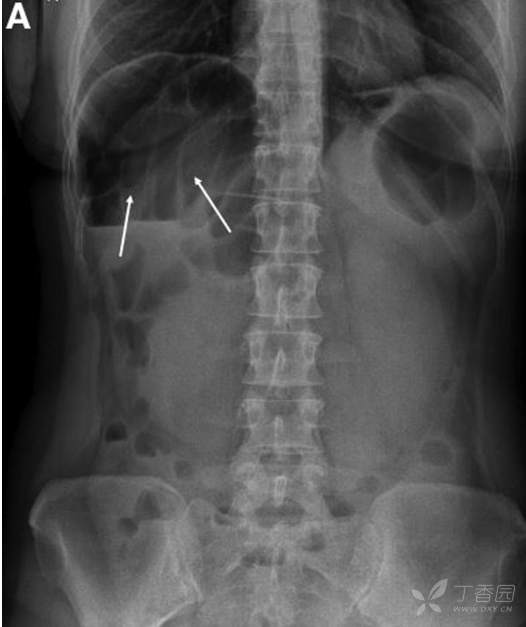

4小时后,患者因严重腹痛再次来院。查体:体温正常,BP 110/70mmHg,P 70/分,R16/分。全腹弥漫性压痛,叩诊鼓音,腹腔刺激征阴性。

腹部平片如图。